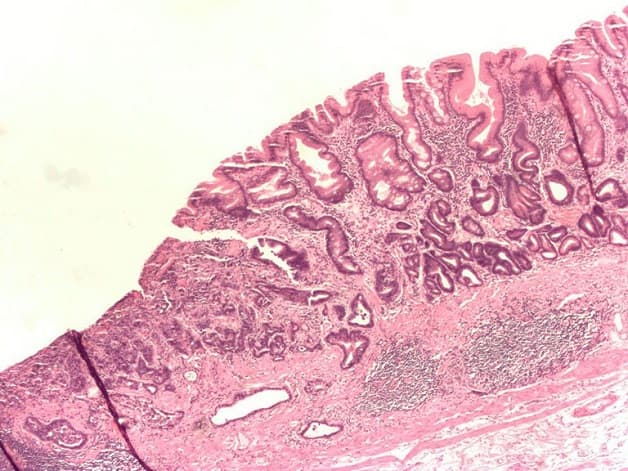

Các tế bào niêm mạc bên trong dạ dày bị tổn thương kéo dài, không được chữa trị kịp thời khiến cho lớp niêm mạc này teo dần. Dị sản ruột dạ dày là tình trạng tiến triển của viêm teo niêm mạc dạ dày. Khi tế bào niêm mạc dạ dày bị teo trong thời gian dài, nó không đảm bảo được các chức năng vốn có dẫn đến phát triển niêm mạc ruột ở dạ dày. Đây được coi là tổn thương tiền ung thư, có thể tiến triển thành ung thư dạ dày nếu không được phát hiện và điều trị kịp thời.

Dị sản ruột dạ dày là tình trạng tiếp theo của viêm teo niêm mạc dạ dày